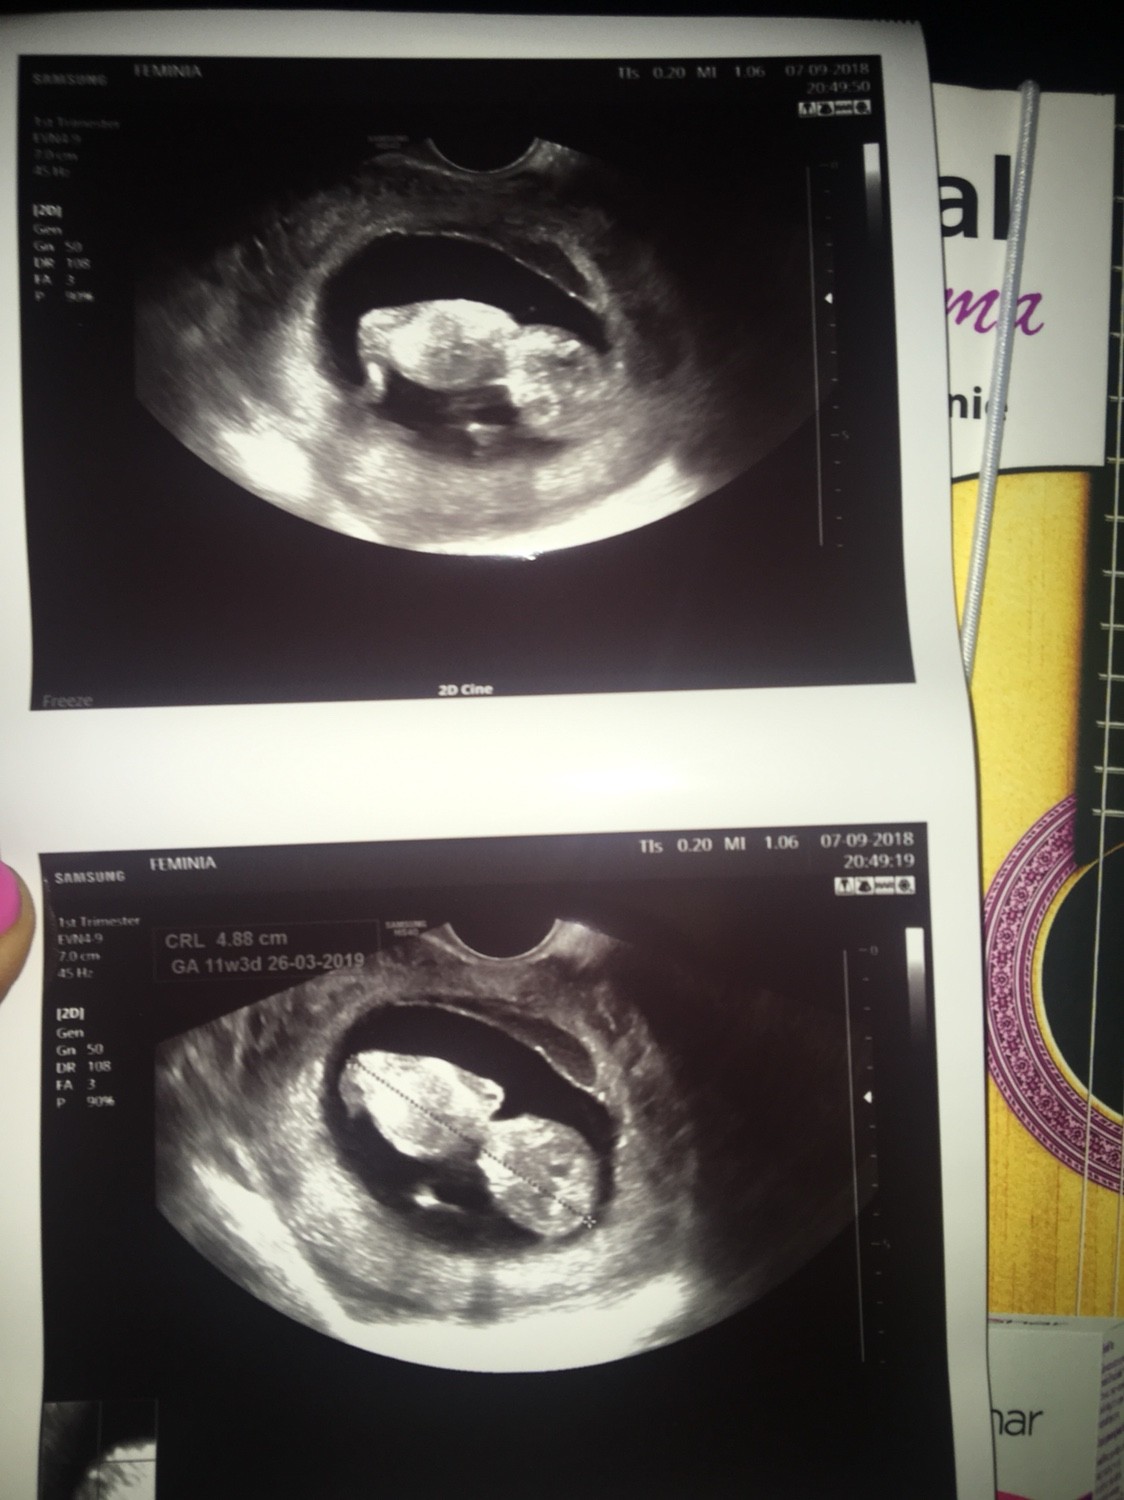

10t6d. 19go kolejna wizyta, poczatek pazdziernika prenatalne. Oby nadal wszystko bylo dobrze

Ja już po wizycie. Wszystkie wyniki badań książkowe. Maluszek ma 16 mm serduszko pięknie biło [emoji16]( lekarz mi je na chwilkę puścił). Tętno płodu 170. Chociaż on tak niewyraźnie pisze że to tylko moje domniemanie.

Kolejną wizyta 08.10. I podczas tej wizyty zrobimy od razu prenatalne pierwszego trymestru.

1536598498377.jpg

• 1536598498377.jpg

373,6 KB · Wyświetleń: 428